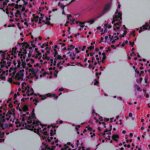

Elevated levels of LDL cholesterol can cause lipid deposits in the walls of blood vessels, usually in the arteries. It is LDL cholesterol that leads to the appearance of atherosclerotic plaques, which narrow the lumen of blood vessels or completely clog them, thereby blocking the flow of blood.

The consequences of atherosclerosis are very severe. This is the development of myocardial infarction, stroke, chronic coronary heart disease, occlusion of peripheral arteries, which can lead to amputation of the lower extremities.